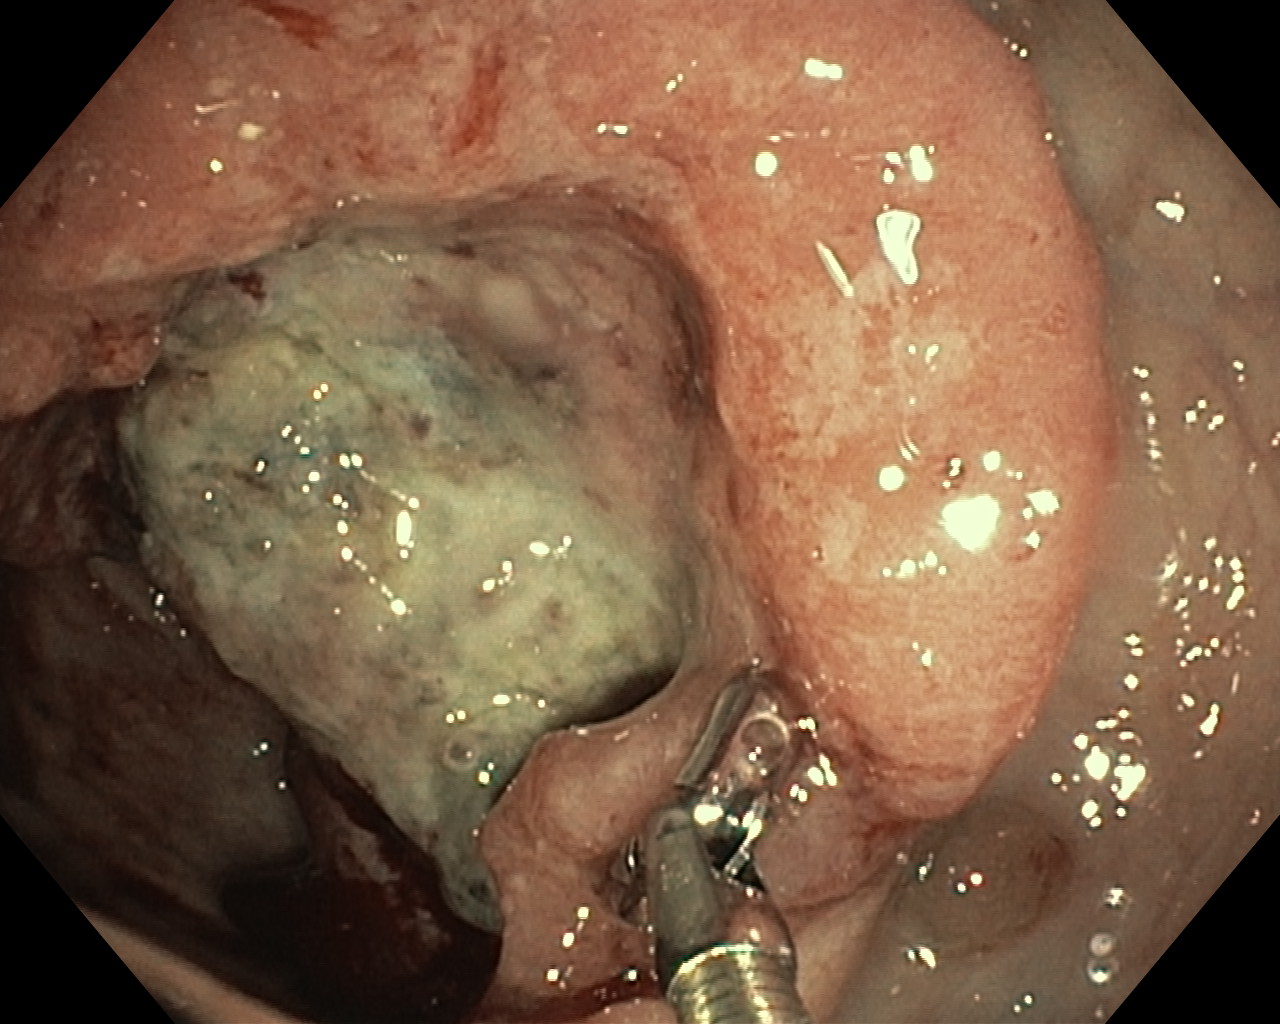

Nowotwory przewodu pokarmowego

Zabiegi endoskopowe